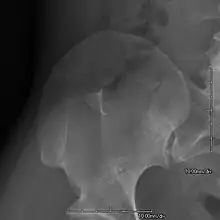

AP radiograph of the right iliac crest showing a bony exostosis or posterior iliac horn, which is pathognomonic of NPS

• Exostoses arising from the posterior aspect of the iliac bones ("iliac horns") are present in as many as 80% of patients; this finding is considered pathognomonic for the syndrome.